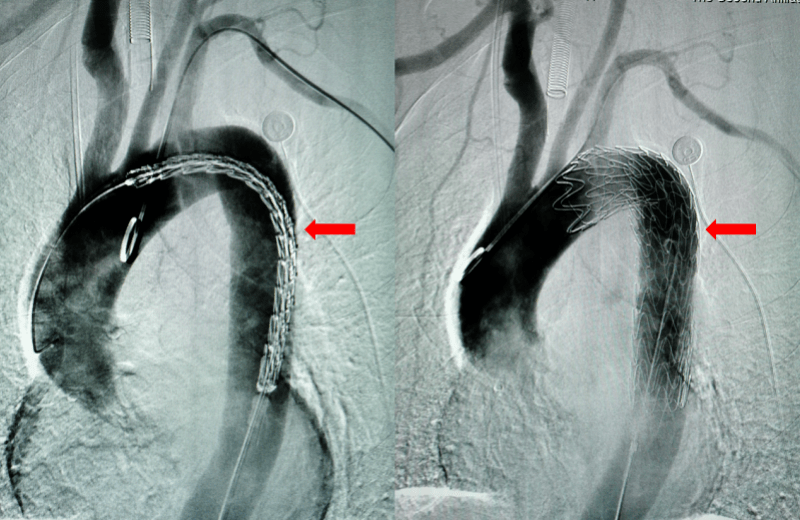

【耳鼻|鱼刺卡喉,吞了口饭险夺命!医生提醒→】MDT团队认为 , 如果应用传统内镜手术或开胸手术取异物都有极大的风险 , 随即决定采用当今先进的主动脉腔内隔绝术治疗 , 通过股动脉途径送入主动脉覆膜支架系统 , 配合内镜下取出卡在食管和胸主动脉中的鱼刺 。 手术在微创介入治疗中心手术室进行 , 麻醉科团队负责全身麻醉 , 先由微创介入科团队预植入主动脉支架 , 然后消化内科团队通过内镜取出鱼刺后立即释放支架封堵主动脉破口 , 耳鼻咽喉科团队负责围手术期的准备及管理 , 心胸外科团队做好了随时转开胸手术的应急方案 。

当一切准备就绪 , 患者全麻后由微创介入科医生将主动脉支架预先植入到位 , 接着消化内科医生在内镜下找到鱼刺并夹住 。 接下来的手术步骤极其关键 , 一旦鱼刺拔出后 , 若主动脉破口封堵不及时 , 就有可能导致大出血 。 因此“拔出鱼刺”和“支架封堵”的手术步骤必须依次无缝连接进行 。 此时 , 消化内科医生与微创介入科医生各就各位 , 在团队密切配合下 , 消化内科吕建忠夹住鱼刺将其拔出 , 内镜下可见鲜血从破口涌出 , 拔出后微创介入科练辉立即释放支架将主动脉破口封堵 , 此时内镜下可见出血马上停止了 。 仅仅用了5秒钟 , 手术的关键步骤顺利完成!操作的无缝连接大大地减少了病人的出血量和降低了死亡的风险!

文章图片

内镜下可见鱼刺刺入食管;用异物钳夹紧鱼刺 。

预先植入主动脉支架 , 待鱼刺拔除后立即释放主动脉支架 , 造影未见对比剂外溢表现(无出血) 。